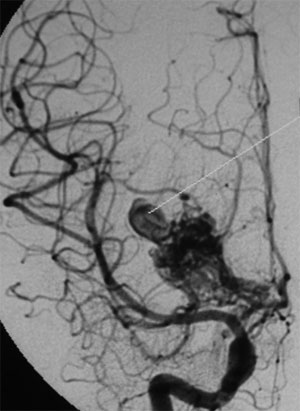

CASO 1 : Embolización de MAV frontal izquierda que presentó hemorragia cerebral resultando en hemiparesia derecha y trastorno del lenguaje

Angiografía antes del tratamiento por embolización. Se muestran por lo menos dos aneurismas en el interior del ovillo malformativo